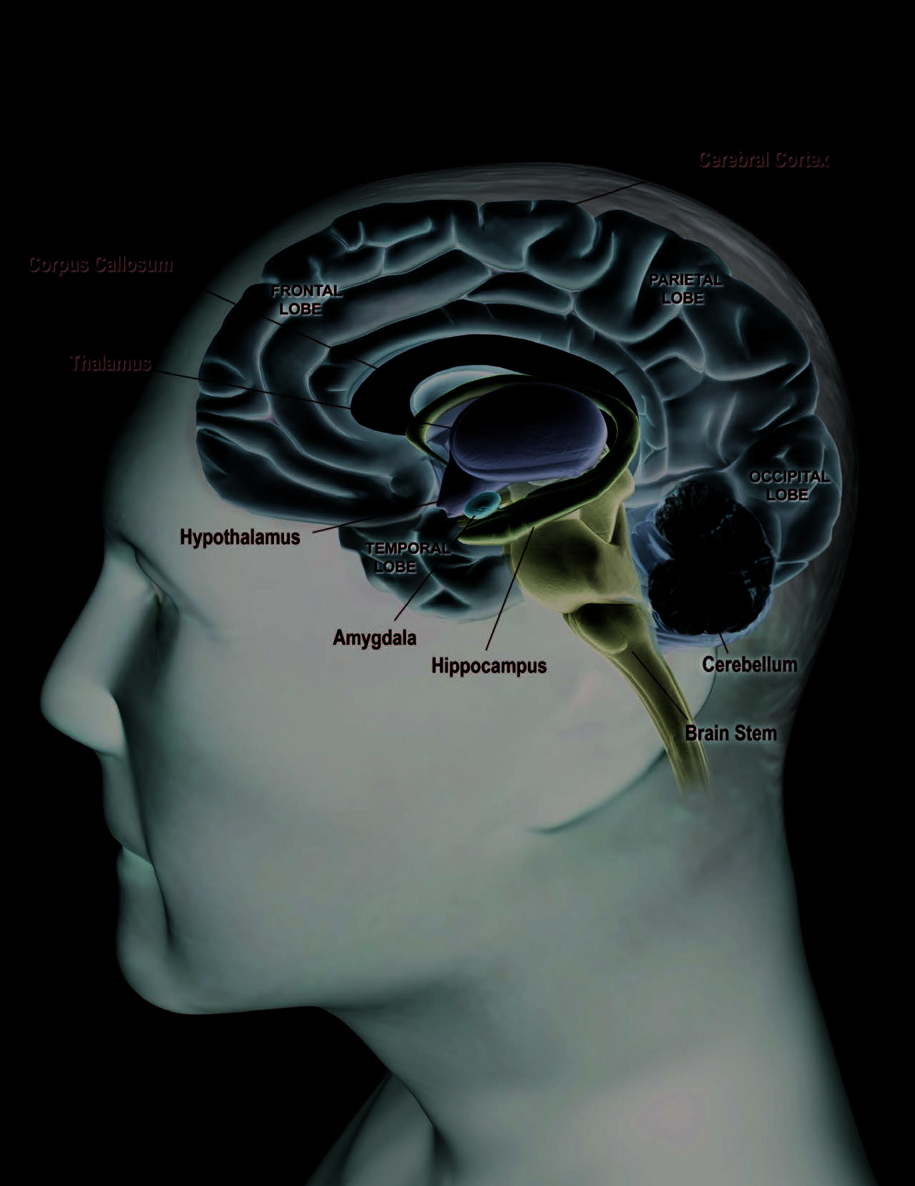

The brain has many parts, each of which ■The occipital lobe, which is at the back of the is responsible for particular functions.

brain, is concerned with vision.

The following section describes a few

■ The temporal lobe, which runs along the

key structures and what they do.

side of the brain under the frontal and pari-

etal lobes, deals with the senses of smell, taste,

THE MAIN PLAYERS

and sound, and the formation and storage of

■ Two cerebral hemispheres account for 85 per-

memories.

cent of the brain’s weight. The billions of neurons

in the two hemispheres are connected by thick

■ The cerebellum sits above the brain stem and

bundles of nerve cell fibers called the corpus cal-

beneath the occipital lobe. It takes up a little more

losum. Scientists now think that the two hemi-

than 10 percent of the brain. This part of the

spheres differ not so much in what they do (the

brain plays roles in balance and coordination. The

“logical versus artistic” notion), but in how they

cerebellum has two hemispheres, which receive

process information. The left hemisphere appears

information from the eyes, ears, and muscles and

to focus on details (such as recognizing a particular

face in a crowd). The right hemisphere focuses on

broad background (such as understanding the rela- Front View of the Brain tive position of objects in a space). The cerebral

hemispheres have an outer layer called the cerebral

cortex. This is where the brain processes sensory

information received from the outside world,

controls voluntary movement, and regulates

cognitive functions, such as thinking, learning,

speaking, remembering, and making decisions.

The hemispheres have four lobes, each of which

has different roles:

■ The frontal lobe, which is in the front of the

brain, controls “executive function” activities

like thinking, organizing, planning, and

problem solving, as well as memory, attention,

and movement.

■ The parietal lobe, which sits behind the

frontal lobe, deals with the perception and

integration of stimuli from the senses.

Side View of the Brain

This illustration shows a three-dimensional side

view of one of two cerebral hemispheres of the brain.

To help visualize this, imagine looking at the cut side

of an avocado sliced long ways in half, with the

pit still in the fruit. In this illustration, the “pit” is

several key structures that lie deep within the brain

(the hypothalamus, amygdala, and hippocampus)

and the brain stem.

■ The hippocampus, which is buried in the

Once the cerebellum processes that information, it temporal lobe, is important for learning and sends instructions to the body through the rest of

short-term memory. This part of the brain is

the brain and spinal cord. The cerebellum’s work

thought to be the site where short-term

allows us to move smoothly, maintain our balance, memories are converted into long-term and turn around without even thinking about it. It memories for storage in other brain areas.

■ The thalamus, located at the top of the brain

bering how to do things like drive a car or write

stem, receives sensory and limbic information,

your name.

processes it, and then sends it to the cerebral

■ The brain stem sits at the base of the brain. It

cortex.

connects the spinal cord with the rest of the brain. ■ The hypothalamus, a structure under Even though it is the smallest of the three main

the thalamus, monitors activities such as body

players, its functions are crucial to survival. The

temperature and food intake. It issues instructions

brain stem controls the functions that happen

to correct any imbalances. The hypothalamus also

automatically to keep us alive—our heart rate,

controls the body’s internal clock.